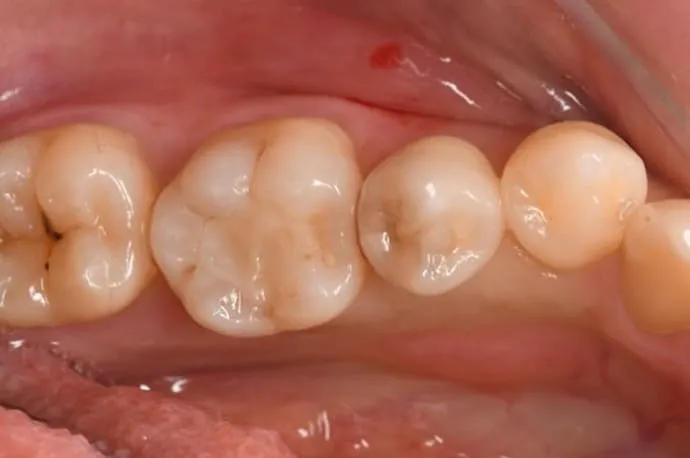

中程度の虫歯:詰め物(インレー)

治療回数 2回

術後の痛み 虫歯が深い場合、冷たい物でしみたり、噛むと痛みが出ることがあります。型採りから詰め物完成まで仮の蓋で過ごすため、噛み合わせによって痛みが出ることもあります。痛みが強い場合や続く場合は追加治療を行うことがあります。

虫歯を除去した後、範囲が大きい場合は樹脂では強度不足になるため型採りを行います。歯型は歯科技工士に送り、模型をもとに詰め物を作成。問題がなければ、次回の来院時に装着します。

詰め物には、保険診療と自費診療の素材がいくつかあります。それぞれ特徴が異なりますので、患者さまのお口の状態に合った最適な材質についてはご相談ください。